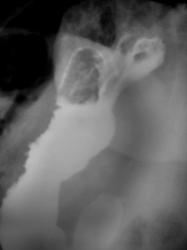

Пациент направлен на рентгенологическое исследование ЖКТР врачом терапевтом с диагнозом - "Хронический гастрит". В процессе проведения рентгенологического исследования выявлена грыжа пищеводного отверстия диафрагмы. Ваше мнение коллеги?

Картина фиксированной осевой (аксиальной) грыжи пищеводного отверстия диафрагмы, вероятно врожденный короткий пищевод (на снимке №11 виден его небольшой изгиб, но для полноценного пищевода этого недостаточно). Нарушение функции замыкающего механизма кардии. Насчет желудочно - пищеводного рефлюкса без скопии по одним снимкам неясно, во всяком случае явной перестройки складок нижних отделов пищевода нет.

Безусловно всей необходимой инфрмацией может располагать только врач проводивший конкретное исследование. Однако на всех представленных рентгенограммах нет снимка, где бы кардиальный отдел желудка был на своем законном месте - ниже купола диафрагмы, а это признак фиксированности грыжы. Хочу подчеркнуть, что неправомерно употребляемый часто нами, рентгенологами, термин "скользящая грыжа" есть не что иное - как синоним термина " аксиальная" (в отличие от параэзофагеальной), а вовсе не отражение состояния фиксированности (невправимости) или нет.